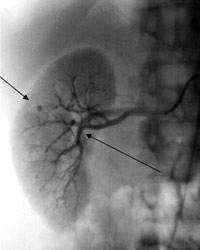

1. Артериография — исследование артерий с введением контрастного вещества, после чего выполняется серия рентгеновских снимков. У пациентов могут быть обнаружены аневризмы и окклюзия артерий.

Узелковый периартериит © Periarteritis nodosa in childrenУзелковый периартериит © Periarteritis nodosa in children